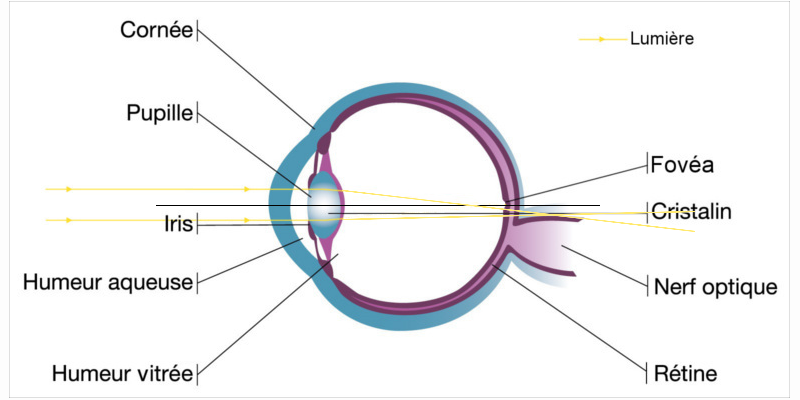

L’œil est composé de deux organes qui sont responsables de la réfraction de la lumière, c'est-à-dire responsables de notre bonne vision, à savoir la cornée et le cristallin.

Ces deux parties de l’œil sont censées être sphériques pour que la puissance soit la même partout. Cependant cela reste théorique car dans la pratique la puissance de l’œil est rarement la même partout et il se peut que le rayon de courbure soit plus important dans certaines partie de l’œil.

Si l’œil a une légère déformation au niveau de la cornée ou du cristallin, cela va engendrer ce que l’on appelle un cylindre, et c’est pour cela que les patients atteints d’astigmatisme ont besoin d'un cylindre avec un axe dans leur correction pour corriger ce défaut.